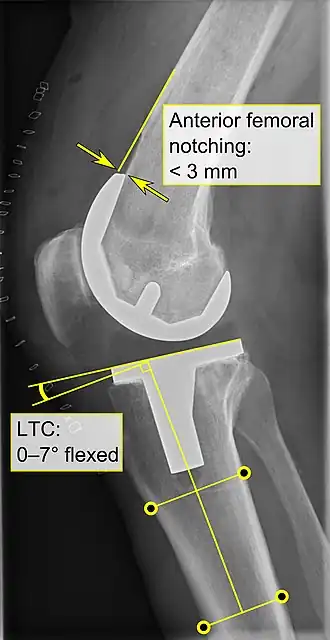

El reemplazo de rodilla se evalúa de forma rutinaria mediante rayos X, incluidas las siguientes medidas:

- La entalladura femoral anterior (el componente femoral que causa una reducción del grosor del fémur distal en la parte anterior) parece aumentar el riesgo de fracturas cuando excede aproximadamente 3 mm.[56]

- CTL: ángulo del componente tibial lateral (o sagital), que está idealmente posicionado de modo que la tibia esté flexionada de 0 a 7° en comparación con un ángulo recto con la placa tibial.[55]